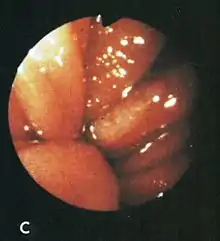

Red, congested folds with blood on a Cameron lesion.

After aspirating some air through the endoscope, this lesion was seen rubbing against opposite folds at the diaphragm level on respiration.

Based on their surgical observations, Windsor and Collis in 1967[4] proposed that blood loss was due to local trauma to the stomach where it rides to and fro in the hiatus on respiration. Boutelier et al.[8] noted on gastroscopy ulcers and erosions at the level of the neck of the hernia in individuals with acute and chronic bleeding, but no detailed description was given. Cameron and Higgins in 1986[1] described linear gastric erosions, later called "Cameron lesions", in people with x-rays showing one-third or more of the stomach above the diaphragm.[9][10][11][12][13][14][15] (figure 1). Over 6 years, Cameron and Higgins studied 109 persons with large hiatal hernias, 55 with anemia and 54 without anemia, at esophagogastroduodenoscopy. Cameron lesions, often multiple, were found at or near the level where the herniated stomach was constricted by the diaphragm. The lesions were typically white, superficial, linear, and oriented along the crests of inflamed appearing mucosal folds (figure 2). Small amounts of blood were often seen on the lesions (Fig 3). Mucosal folds at the diaphragm level were often seen rubbing against each other on respiration (Fig 4). It was proposed that the lesions were caused by mechanical trauma at the level of constriction by the diaphragm [1] Cameron lesions were found in 42% of persons with anemia compared to 24% in those without anemia, a statistically significant difference, p<0.05. Spots of fresh or clotted blood were seen on the lesions in 25% of persons with anemia compared to 7% without anemia, also a significant difference, p<0.05. In the 109 persons in this study, 15 had reflux esophagitis, 11 had peptic ulcers, and 7 had Barrett's esophagus, but none of these findings correlated with anemia. Thus, in people with large hernias, Cameron lesions with evidence of slow bleeding were associated with iron deficiency anemia.